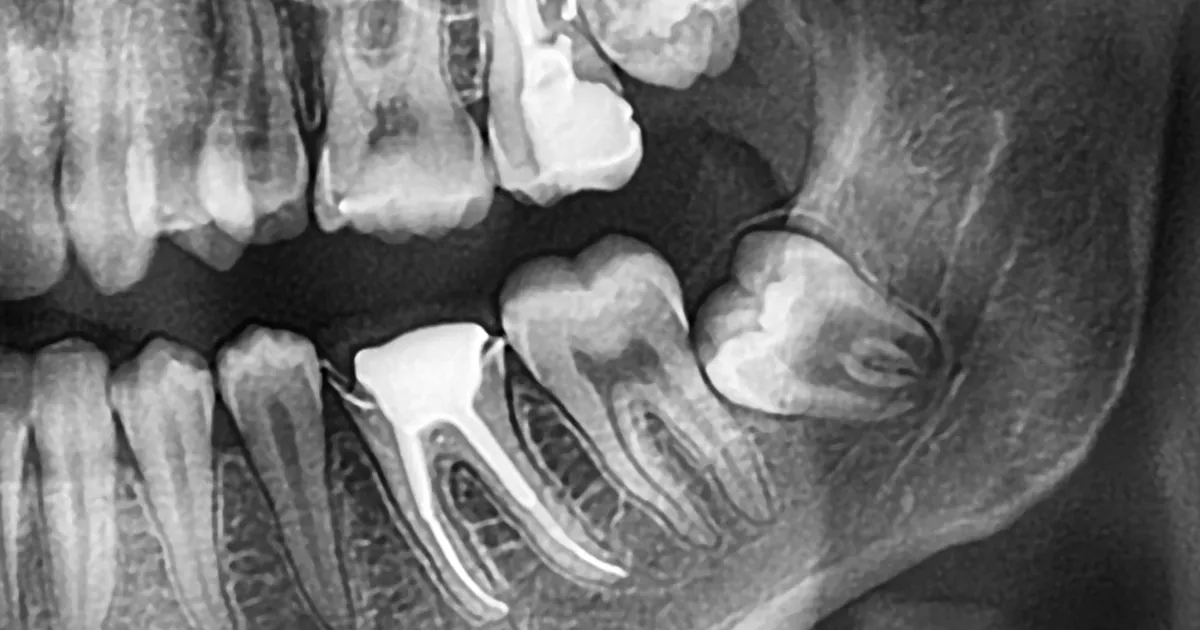

症状复杂的患者

当智齿严重埋伏,或者对邻近的牙齿和骨骼产生影响时,医生可能会建议住院拔除。